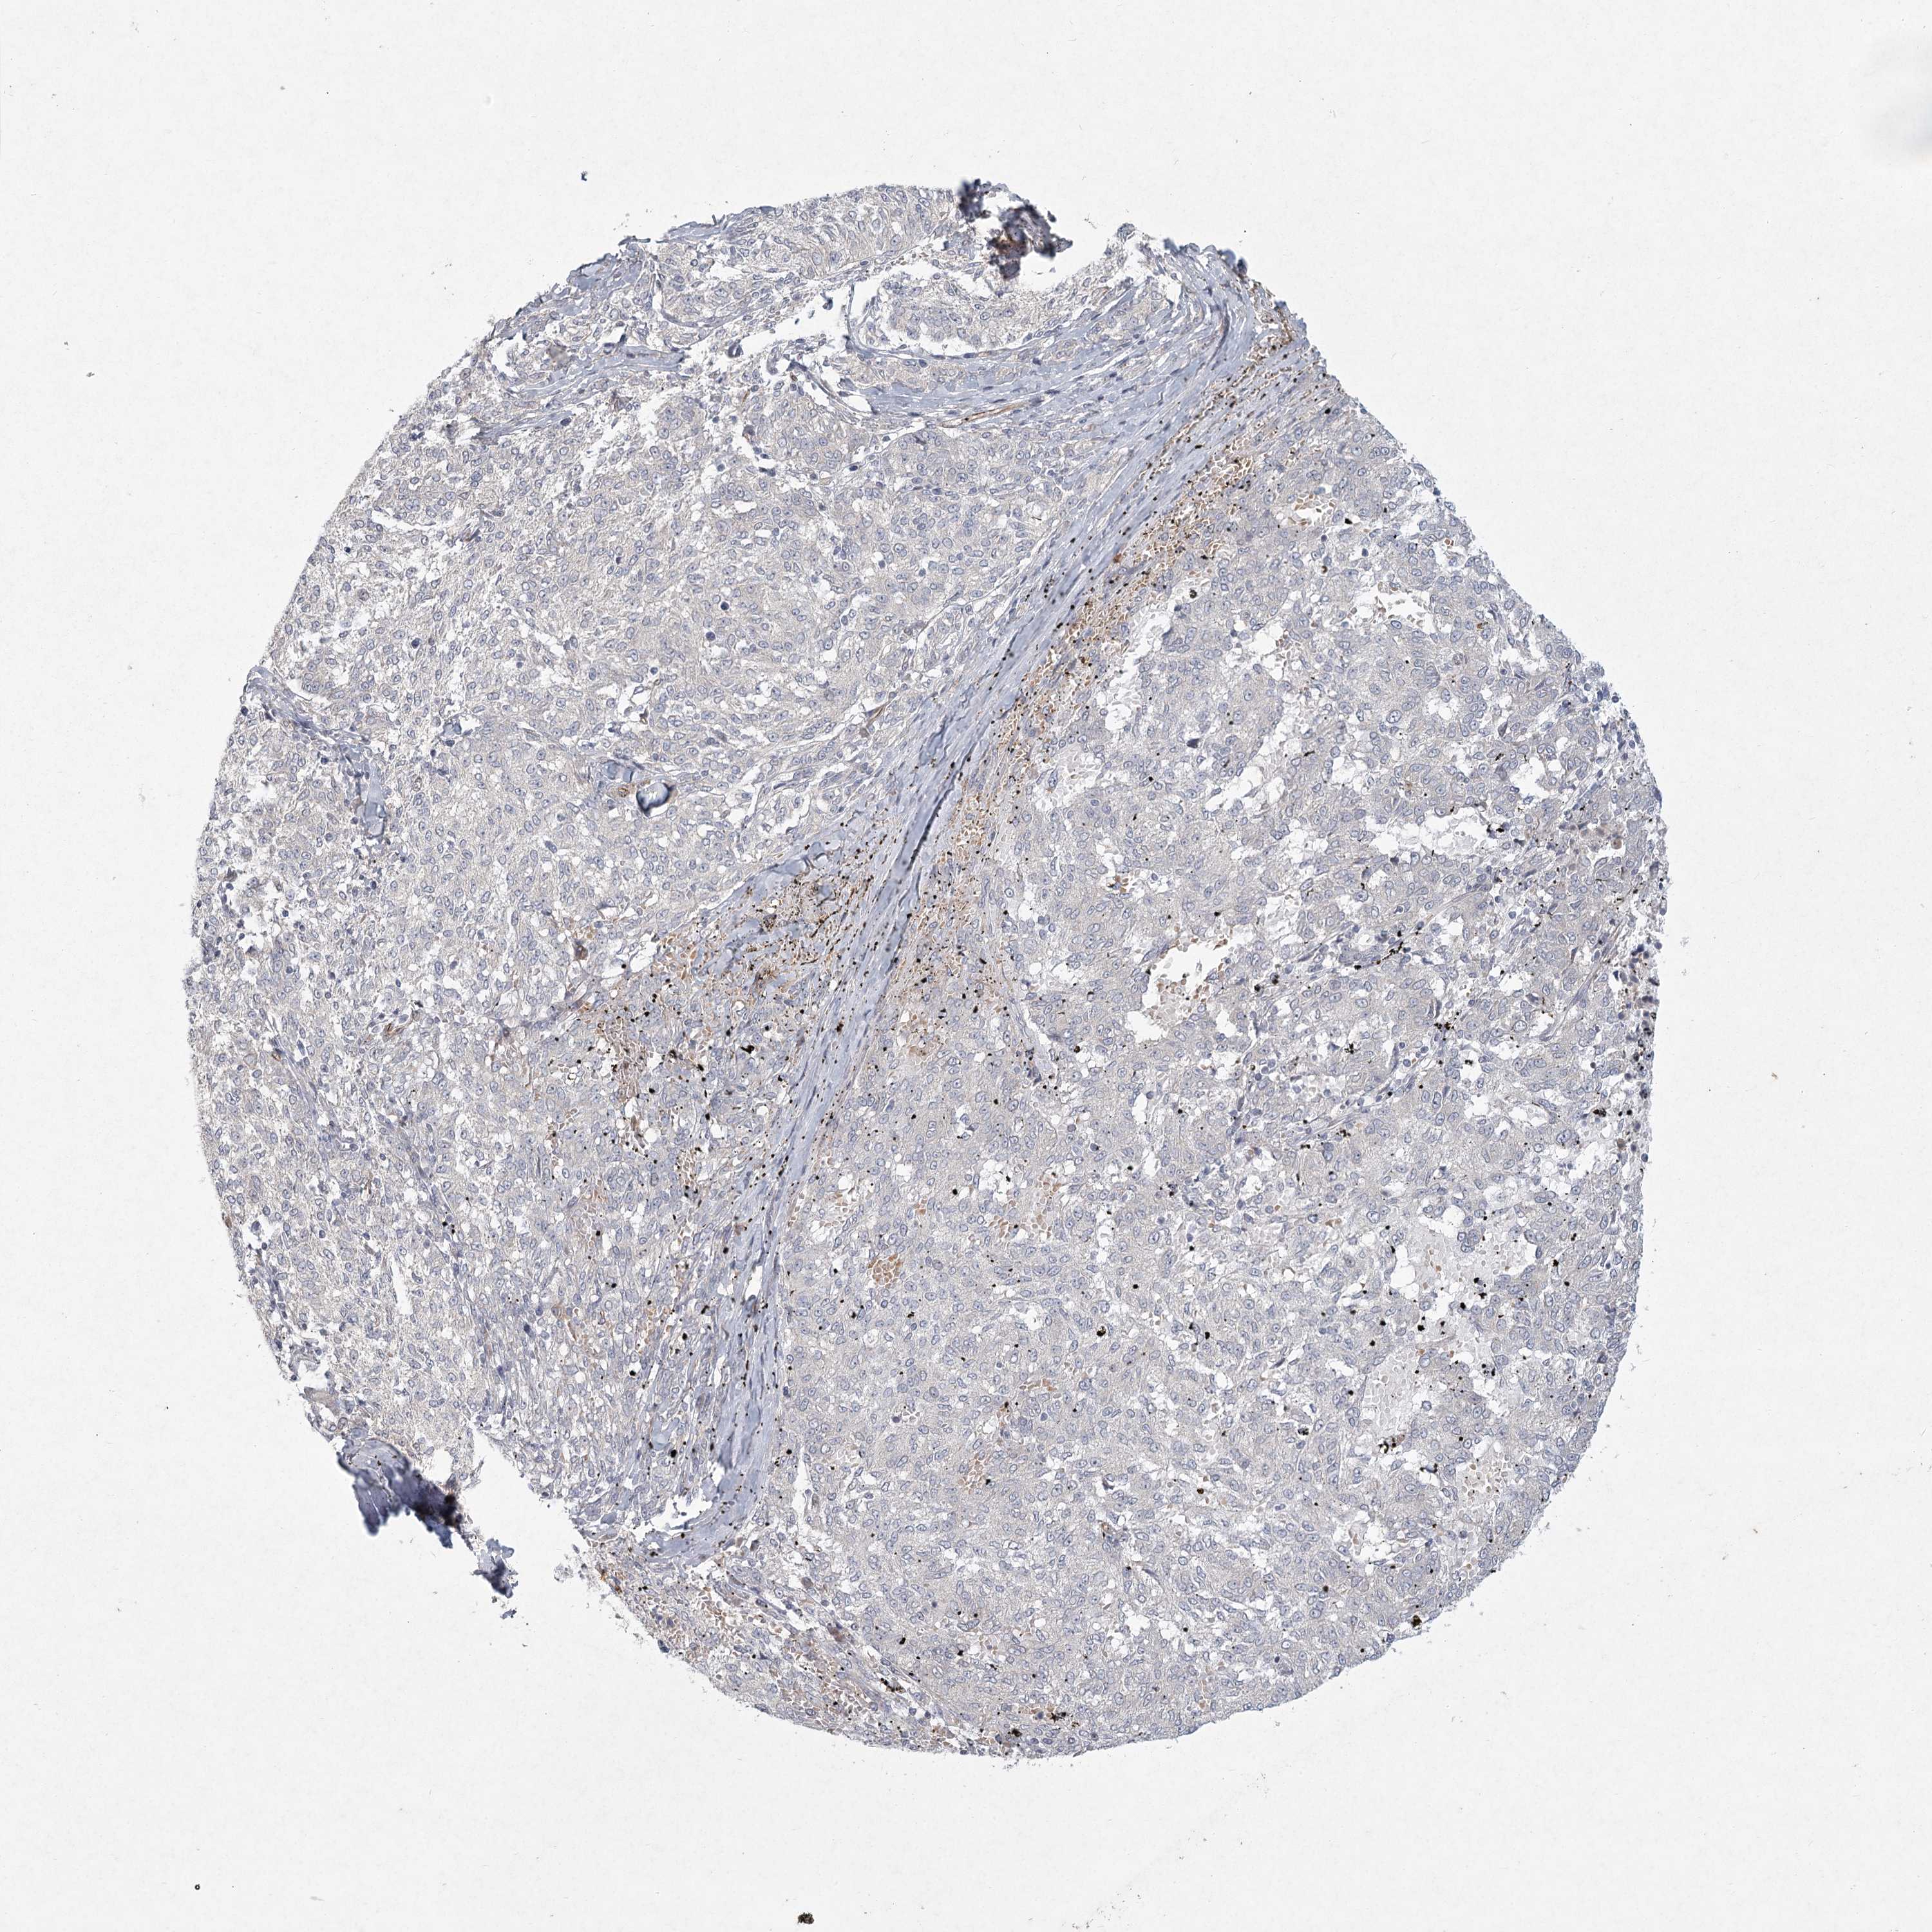

MELANOMA - Protein expressioni

A mouse-over function shows sample information and annotation data. Click on an image to view it in a full screen mode. Samples can be filtered based on level of antibody staining by selecting one or several of the following categories: high, medium, low and not detected. The assay and annotation is described here.

Note that samples used for immunohistochemistry by the Human Protein Atlas do not correspond to samples in the TCGA dataset.

Antibody stainingi

Antibody staining in the annotated cell types in the current human tissue is reported as not detected, low, medium, or high, based on conventional immunohistochemistry profiling in selected tissues. This score is based on the combination of the staining intensity and fraction of stained cells.

Each image is clickable and will lead to virtual microscopy that enables deeper exploration of all samples and also displays staining intensity scores, fraction scores and subcellular localization as well as patient and tissue information for each sample.

Antibody HPA038003

Antibody HPA038004

Staining

High

Medium

Low

Not detected

Intensity

Strong

Moderate

Weak

Negative

Quantity

>75%

75%-25%

<25%

None

Location

Nuclear

Cytoplasmic/membranous

Cytoplasmic/membranous,nuclear

Malignant melanoma, NOS

Malignant melanoma, Metastatic site